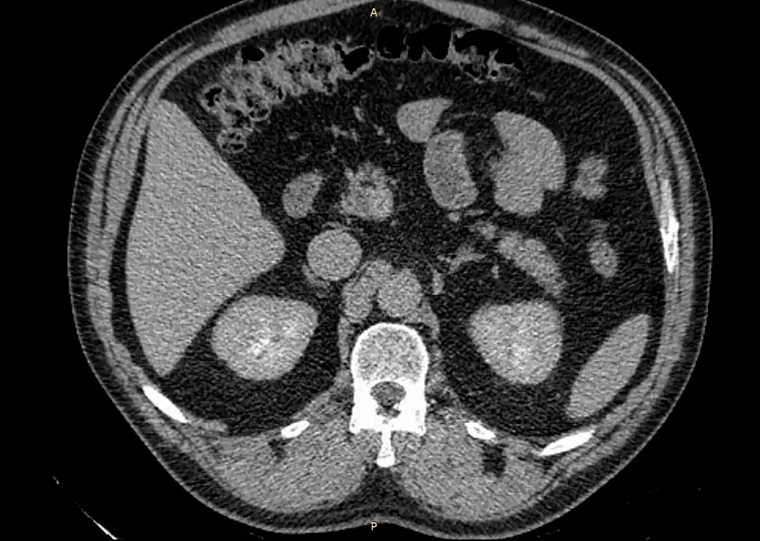

52-летний мужчина наблюдался в поликлинике с доброкачественным новообразованием в почке. Его беспокоили периодические боли в пояснице слева. Ранее выявленная киста почки росла, вызывая нарушение оттока мочи и угрозу снижения функции почки.

Хирургическое удаление кисты в данном случае было невозможно из-за расположения кисты внутри почки. Вмешательство могло привести к потере органа. Урологи МСЧ «Нефтяник» приняли решение помочь пациенту, выполнив уникальную операцию на почке, описанную и продемонстрированную членом-корреспондентом РАН, профессором А.Г. Мартовым.

«Суть метода заключается в создании сообщения между полостью кисты и чашечно-лоханочной системой почки. Мы изучали КТ-снимки, архитектонику почки, чтобы свести к минимуму определенные риски травмирования сосудов почки. Операция прошла в штатном режиме», — пояснил врач-уролог, заведующий отделением урологии №2 клиники «Нефтяник» Владимир Новоселов.